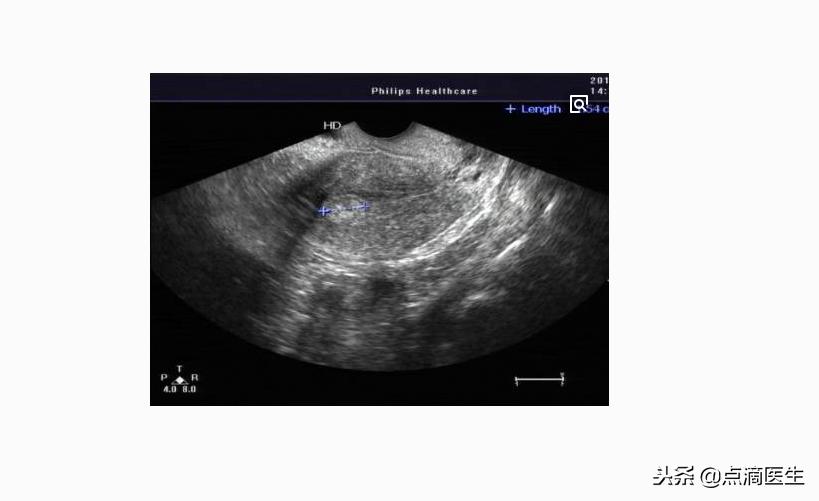

5.动态B超检测卵泡

卵泡B超动态监测

前面四种检测排卵的方法都不能直观看到卵巢、卵泡情况,因为在B超照射下可以很清楚的看到卵泡是否成熟。一般来说,正常的成熟卵泡大小为18~25mm,因此在判断女性是否排卵的方法中B超最为可靠。但是,此方法的局限性在于要多次跑医院,一般时间不够充足的女性往往会错过最佳判断时间。